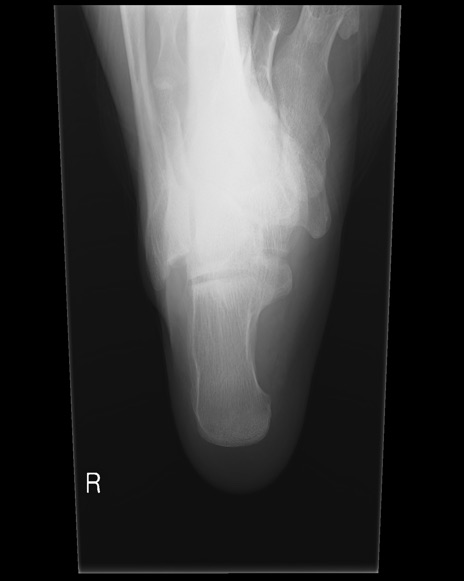

症例37 踵骨レントゲン(右正面像)

踵骨レントゲン